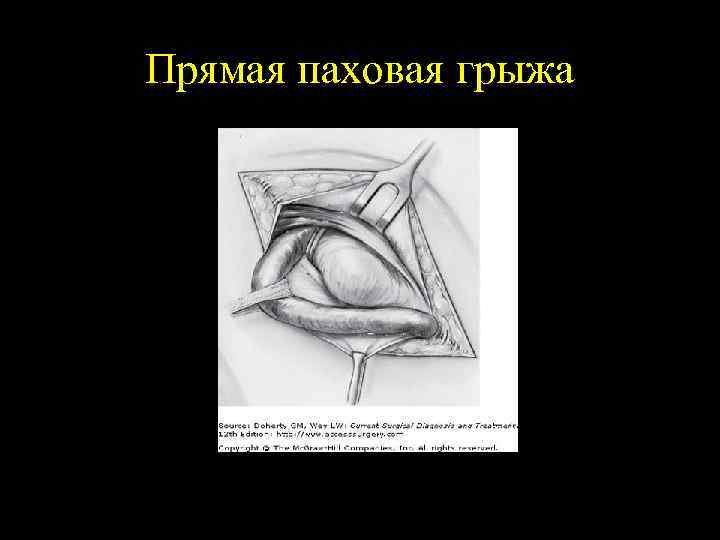

Прямая паховая грыжа

ПРЯМАЯ И КОСАЯ ПАХОВЫЕ ГРЫЖИ